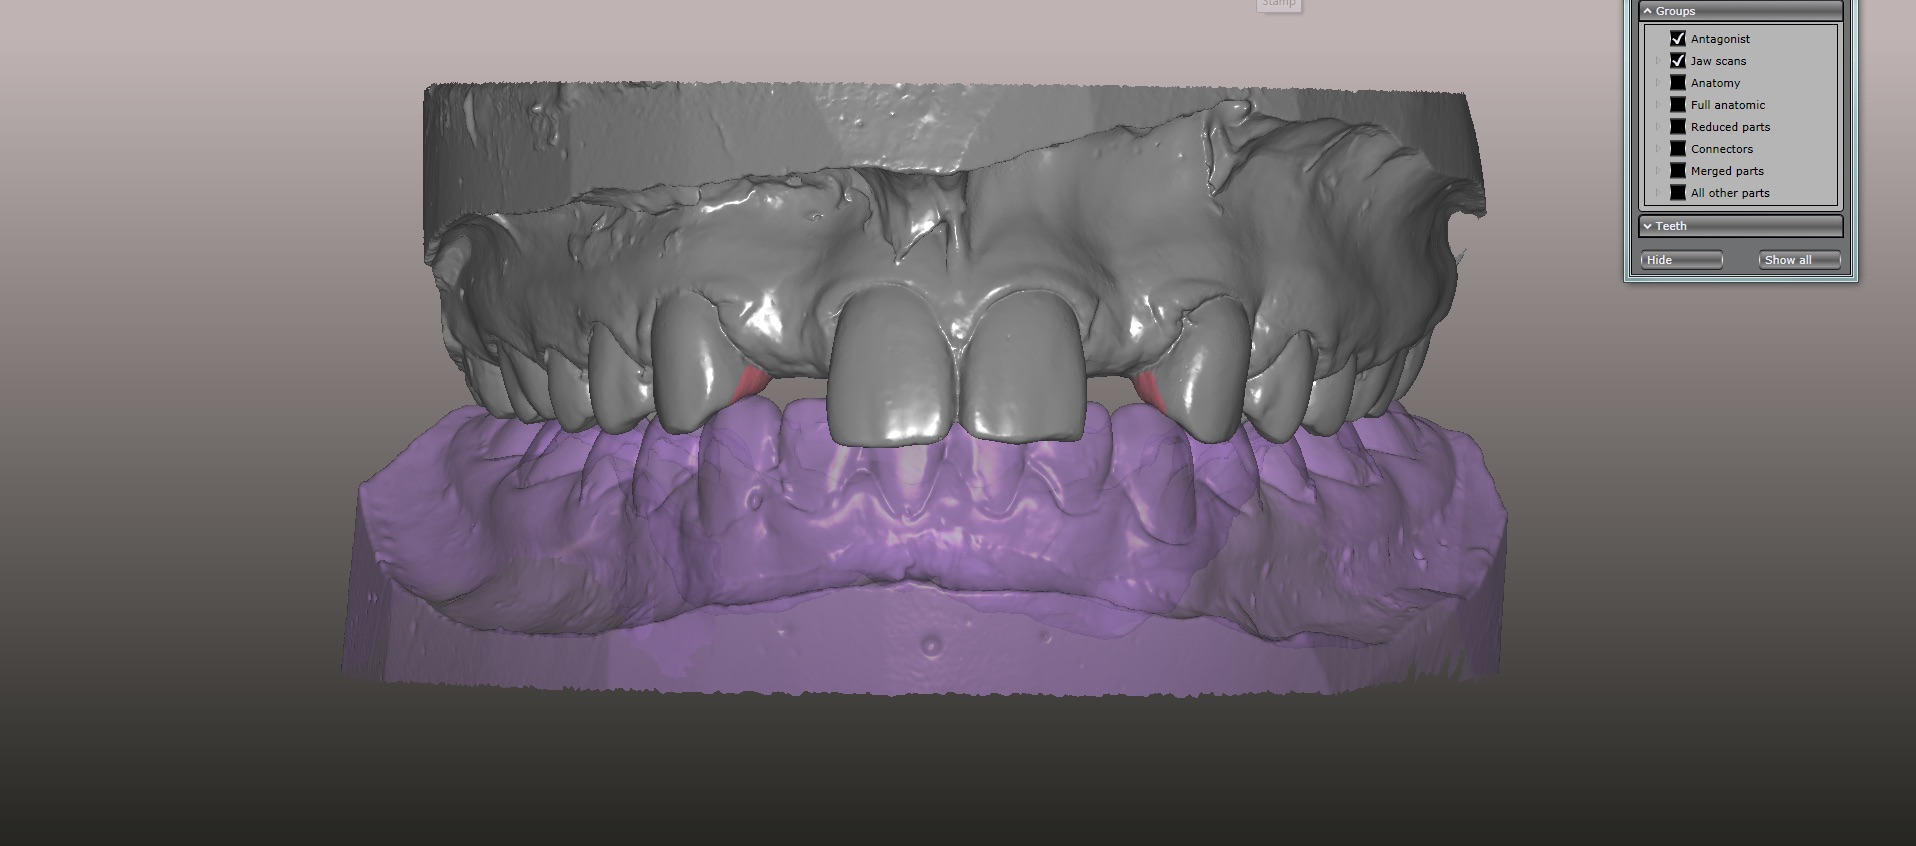

An approach utilizing CAD/CAM was employed to fabricate an accurate fitting, retentive, and esthetic ceramic single-wing resin-bonded bridge. Impressions were taken of the patient and scanned in the laboratory using maximum intensity projection. The scanned models were then used to design the final prosthetic frames utilizing EXOCAD software. The retainer positions and extensions were designed on the models based on the occlusal clearance (Figure 15). Next, the replacement tooth forms were chosen from a virtual library (Figure 16), and try-in PMMA bridge prototypes were milled in Primotec USA PMMA. This allowed for try-in of the design, adjustment of the contacts, and intraoral evaluation of the ridge contact (Figure 17). Once tried and idealized for both fit and occlusion, the design was sent back to the lab to rescan. Utilizing the software, a cut back was made on the lateral incisor (Figure 18), and a 0.3mm space was also virtually designed on the internal surface of the retainer wing to allow layering with feldspathic ceramic (Figure 19). The 0.2 mm internal edge of the wing was designed to be left intact to allow for precise seating and verification of fit on the model. After the frame was milled in zirconia (Zirconzahn, Prettau), it was verified on the model, and high fusing margin porcelain (Noritake CZR) was mixed with a clear utility wax and applied to the internal 0.3 mm depression. This was baked in the oven at a high temperature, allowing the wax to burn out and leaving the feldspathic ceramic fused to the internal surface of the retainer. Once cooled, this was checked for precise fitting on the model and adjustments were made to ensure full seating.

(15.) Models mounted in maximum intensity projection, allowing design of the retainer extensions on the lingual of the canines (in pink).

Figure 15

(16.) Virtual design of anatomic form generated from a virtual library of tooth forms, which was used to fabricate temporary PMMA resin-bonded bridges.

Figure 16